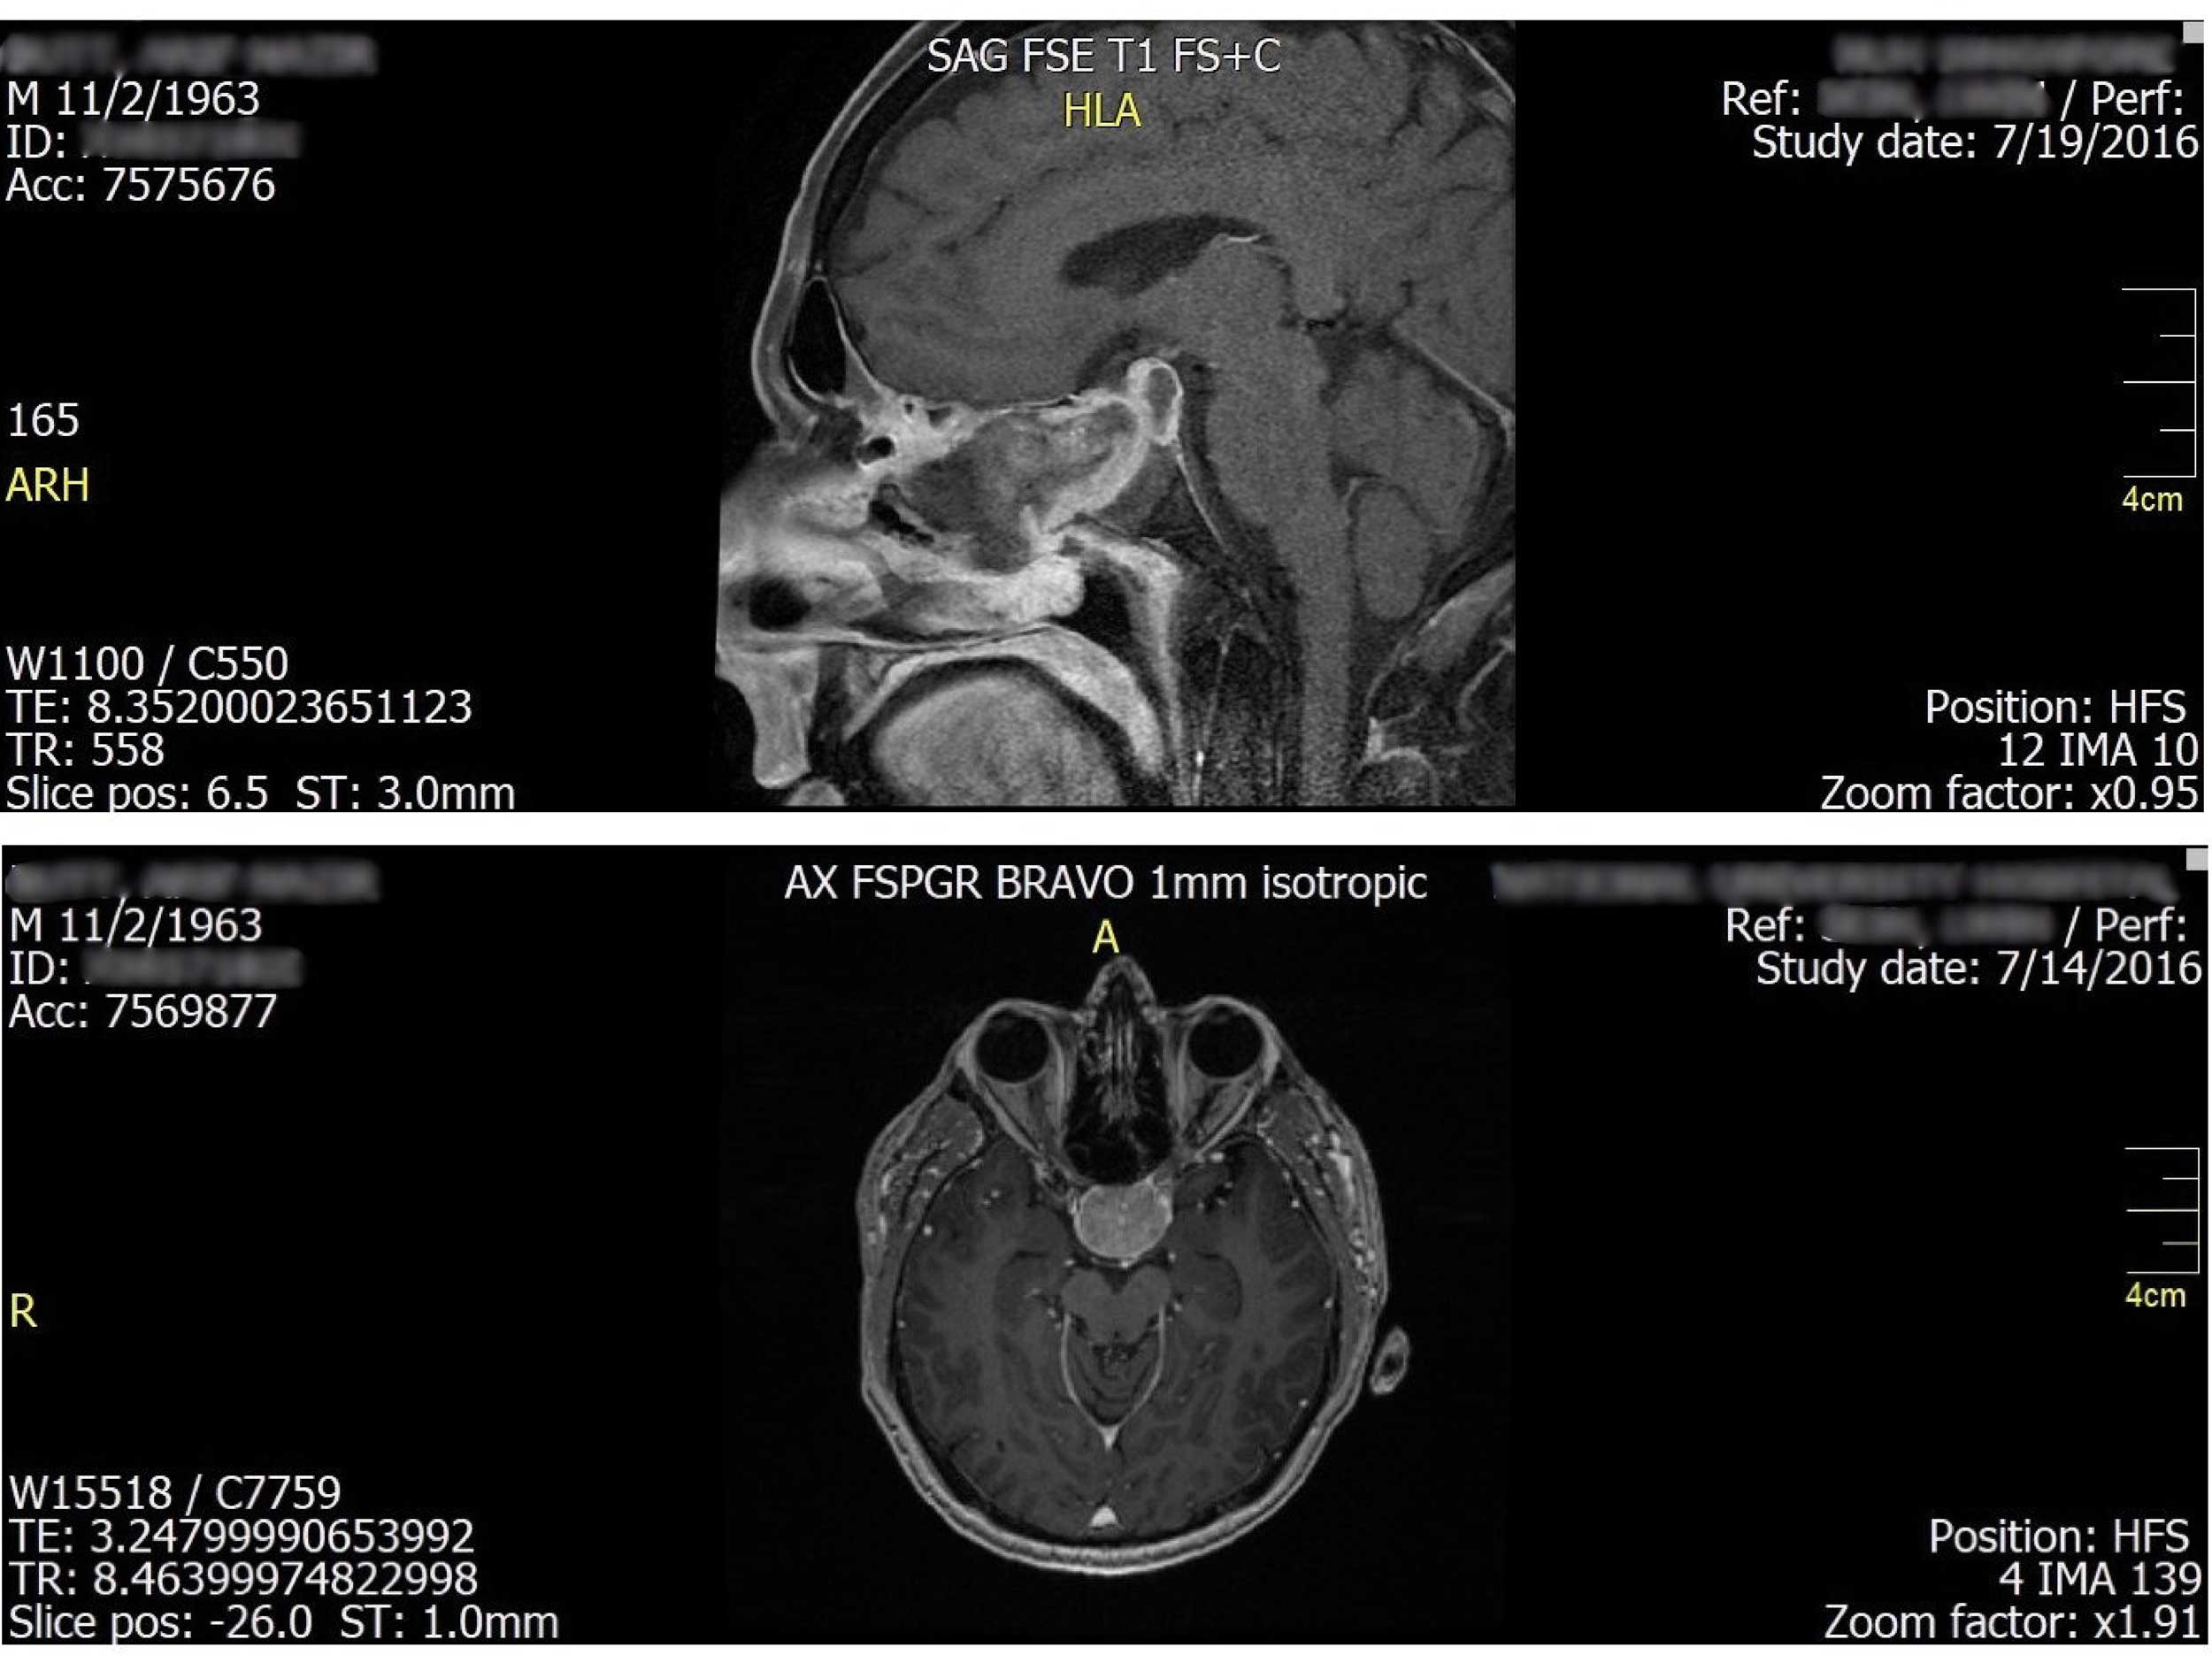

Behind the eyes: Unravelling the mystery of a painless progressive proptosis

Orbital fungal infections have the potential to give rise to serious complications. While these infections typically originate in the sinuses, patients may initially exhibit ocular symptoms. As a result of the diverse and often vague clinical manifestations (especially during the...